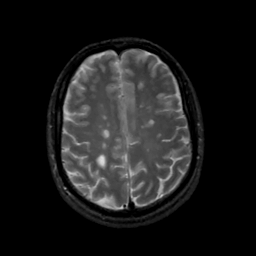

MR Study #14, June 2, 1991 -- Slice #36

[Home][Help][Clinical][Tour 1][Tour 2] Slice 36